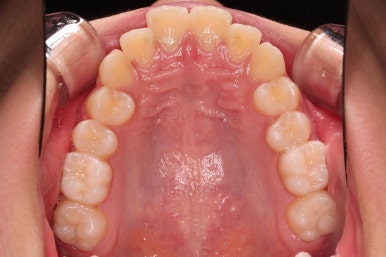

1. 초진 시 입안의 모습 평가

부산치아교정치과 키다리아저씨치과에 처음 내원했을 당시의 입 안의 모습입니다.

전반적으로 윗니가 나와있는 양상이고요.

앞니는 뻐드러져 있네요.

아래 앞니는 위로 솟구쳐 올라서 윗니 뒤쪽을 강하게 치고 있는 과개교합 양상이었고요.

위아래 앞니쪽이 삐뚤어져 있는 상태였습니다.